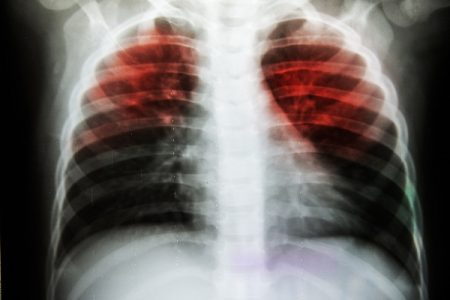

The diagnosis of tuberculosis is based on the detection of the presence of M.tuberculosis in the clinical specimen taken from the patient. The healthcare professional may evaluate the medical history of the patient along with physical examination and X-ray. No single test is used for the diagnosis in all circumstances.

Treatment of tuberculosis is a challenging task because of heterogeneous sites of infection. Even with proper treatment, tuberculosis (TB) can cause major health complications. Lungs are the primary site of infection by M.tuberculosis. If it is left untreated, the disease can cause many fatal complications.